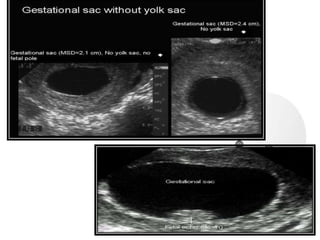

 Anembryonic Pregnancy (blighted ovum) –

pregnancy in which the embryo never

develops or if develops it gets reabsorbed but

the gestational sac normal appearing.

 Multiple Pregnancy- identification of

two gestational sacs indicates twin birth

in 52-63% of cases